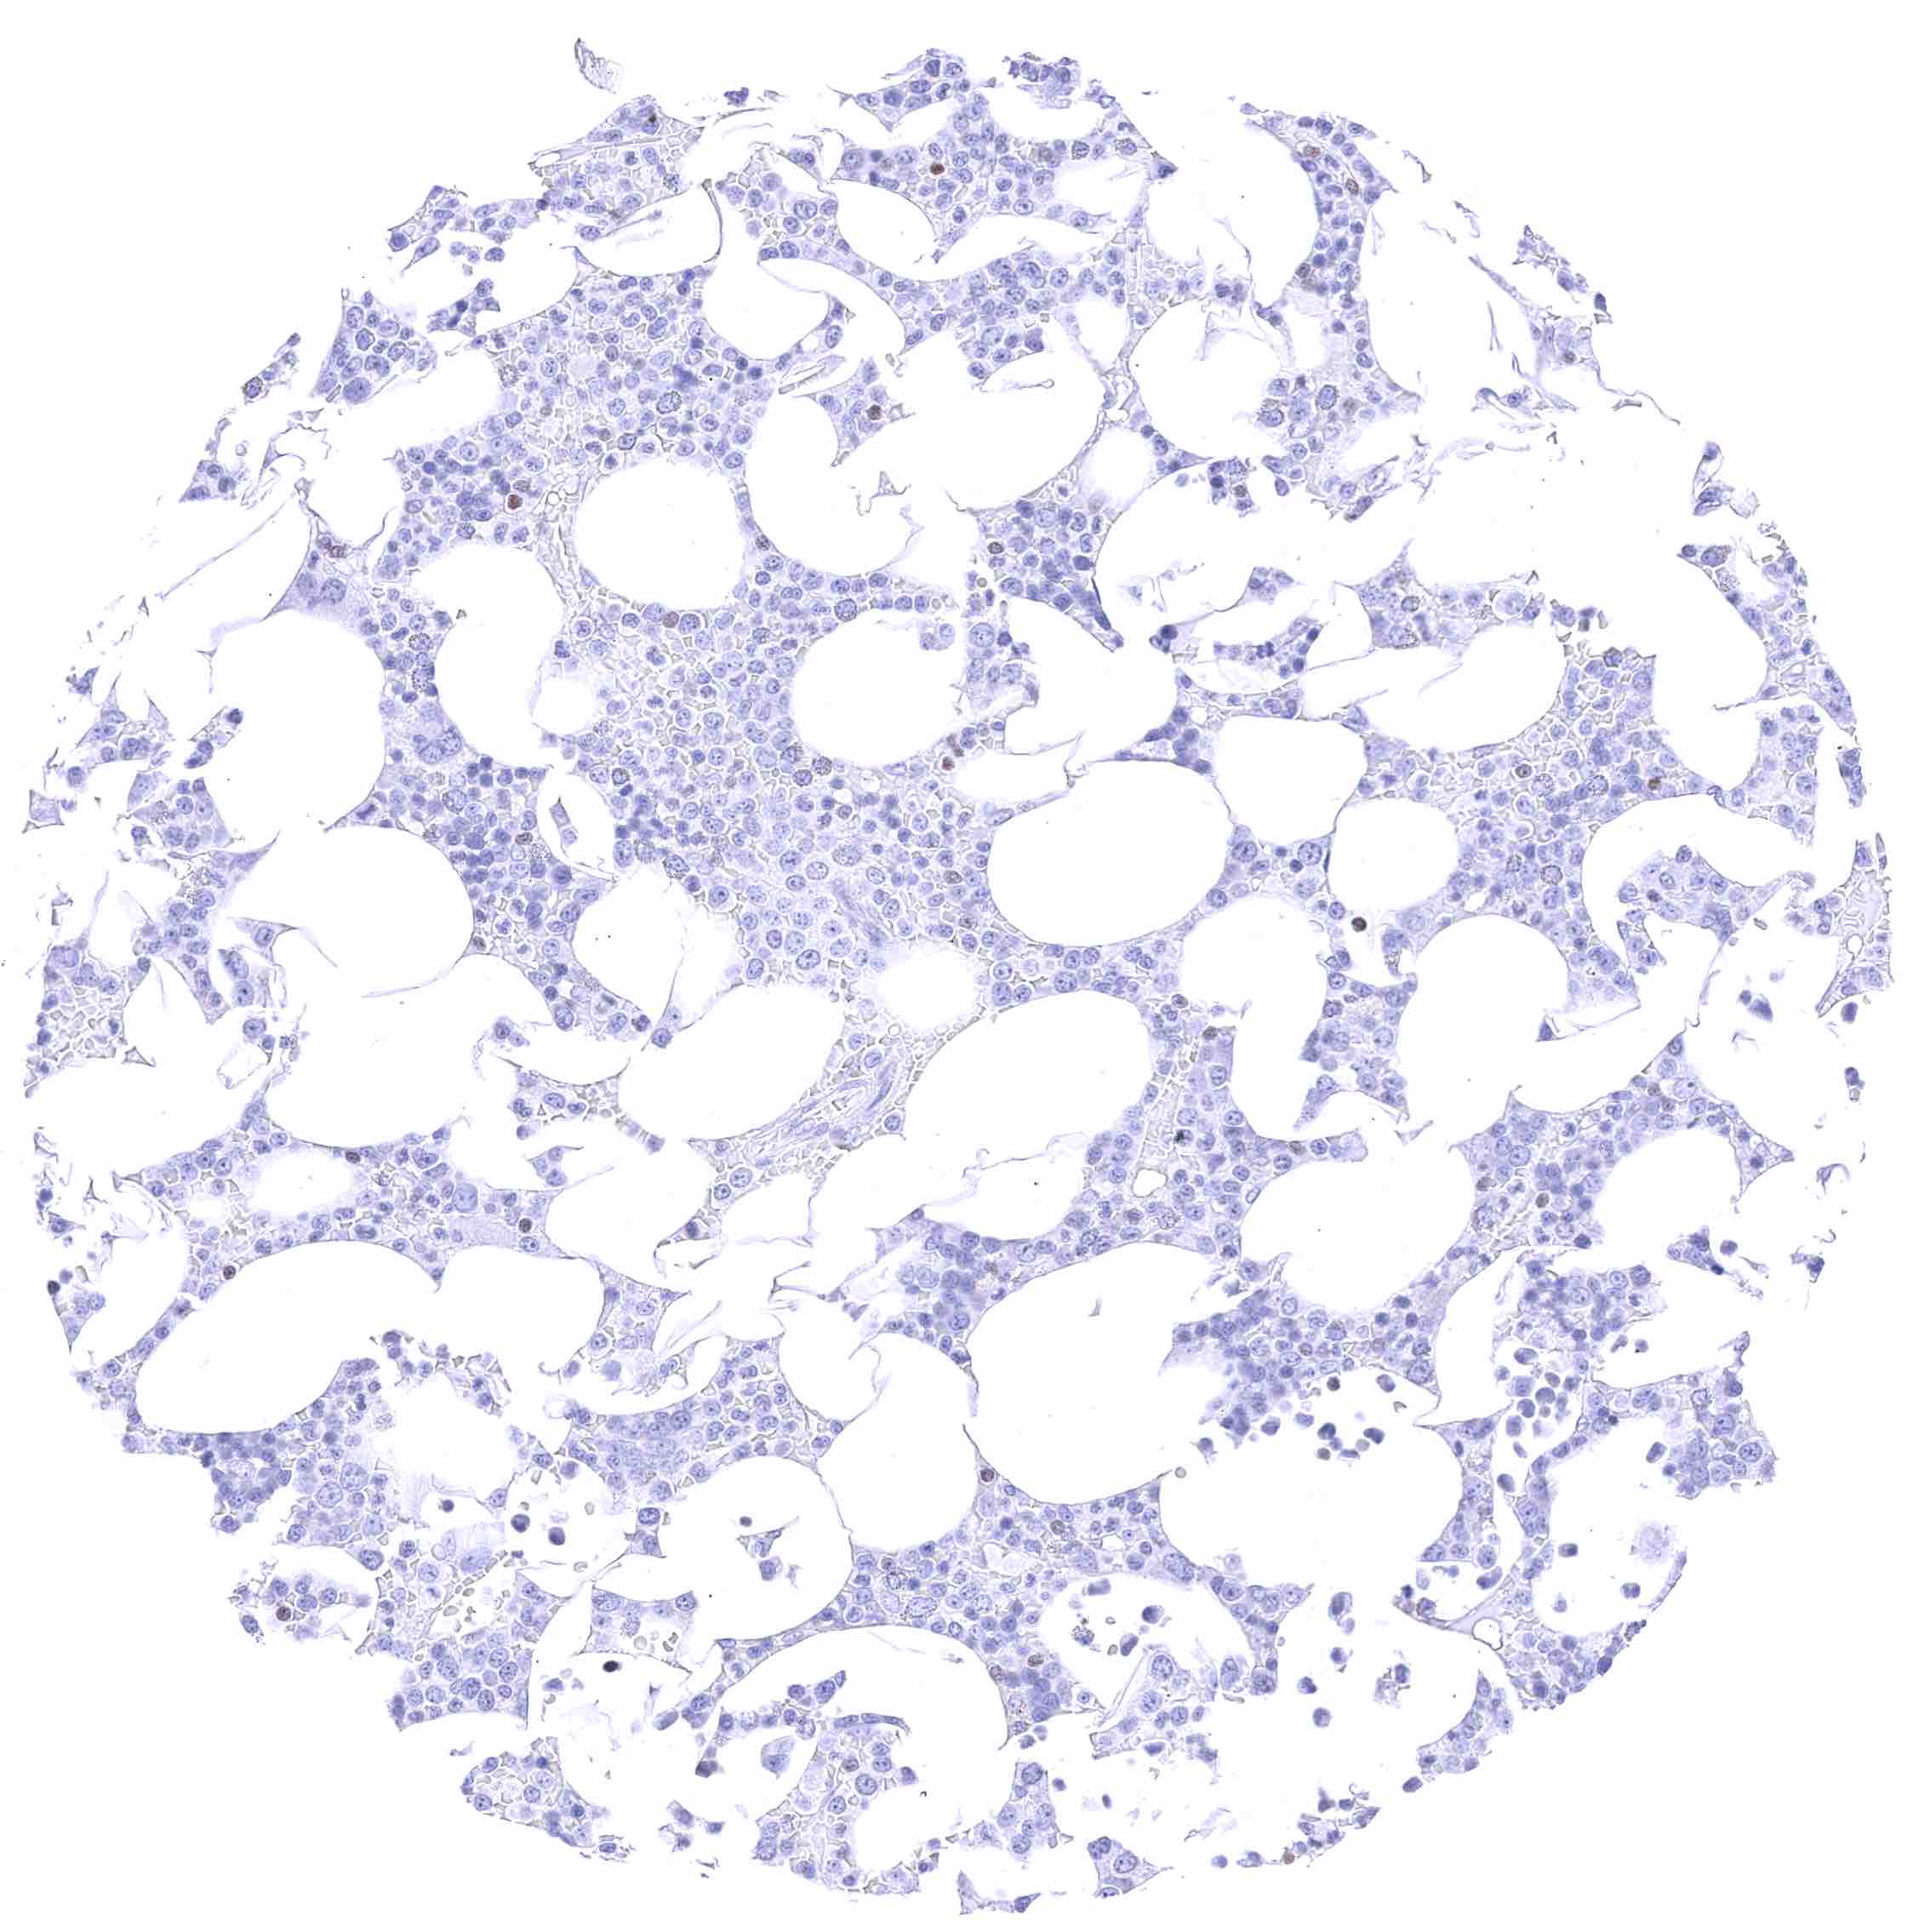

Lymph node – Nuclear GATA3 positivity of numerous lymphocytes.